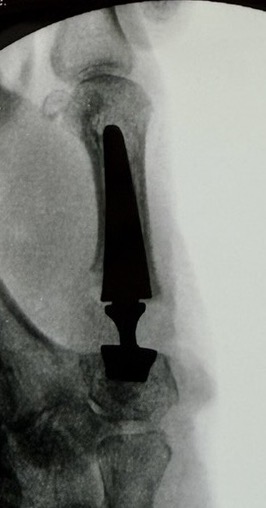

Arthroplasty

Indications

Stage III and IV disease

Low-demand patient

Options

Total joint arthroplasty

Spacer implants

Technique

Vumedi CMC total joint arthroplasty video

Results

Tchurukdichian et al J Hand Surg Eur 2020

- 10 year follow up of 95 total joint replacement (IVORY prosthesis)

- 95% survival rate

- 7% dislocation rate

- 5% revision for fracture or dislocation

Smeraglia et al Int Orthop 2022

- 112 patients with pyrocarbon implant with mean 5 year follow up

- 7 year survivorship 95%

- subluxation rate 17%

- dislocation rate 3%